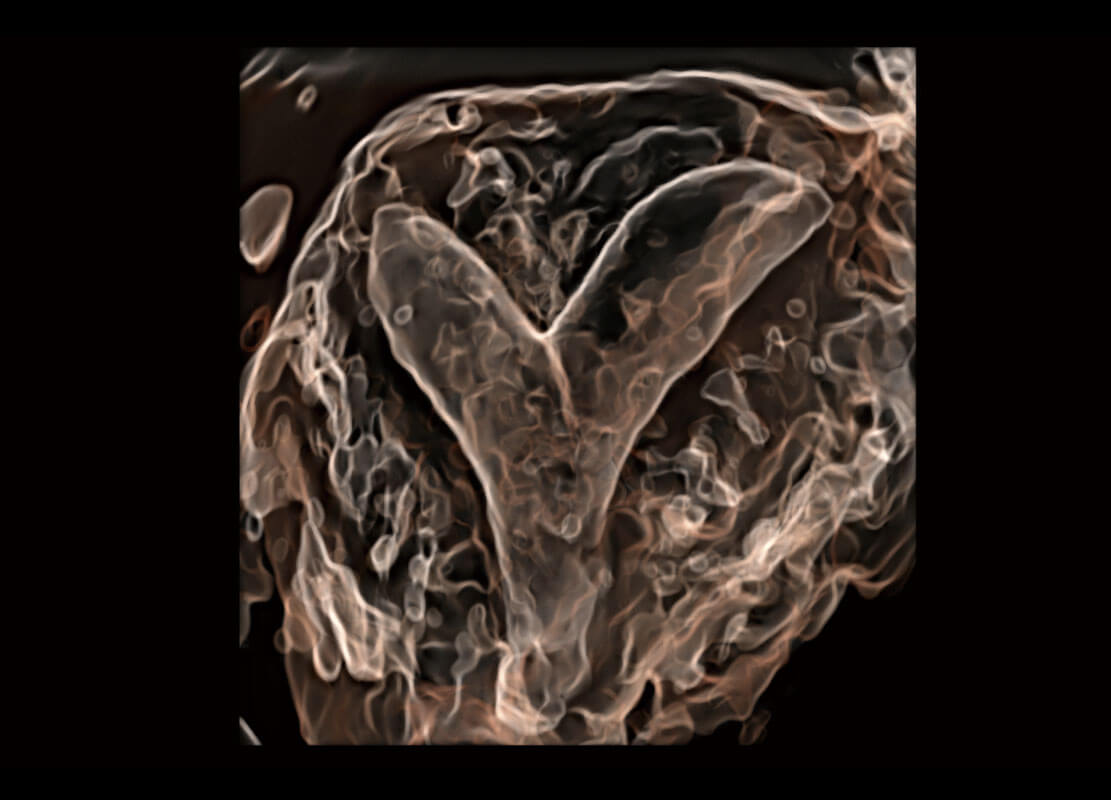

P60搭载一系列胎儿心脏成像技术,实现精细的胎儿心脏评估。

右室双出口

胎心容积成像